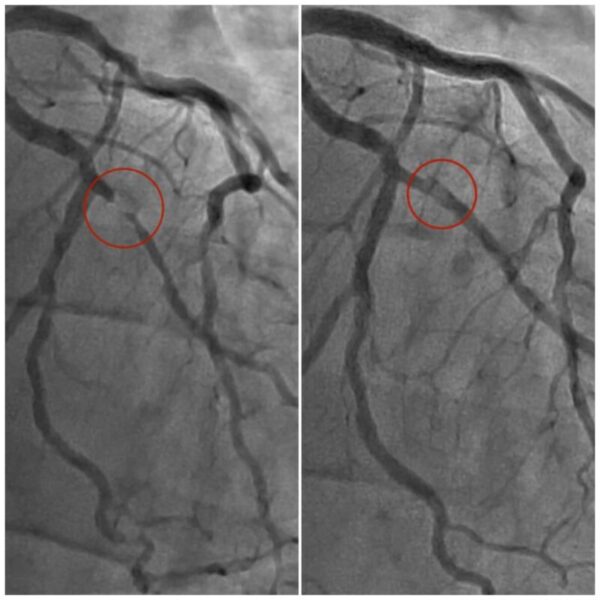

“Це був передінфарктний стан. Це вже критичний момент, коли така сильна задишка у пацієнта з’являється навіть у стані спокою. Ми одразу провели коронарографію і виявили багатосудинне ураження коронарних артерій”, – говорить завідувач відділення кардіології та інвазивної терапії Лікарні Святого Пантелеймона.

“Під час виконання цієї малоінвазивної внутрішньосудинної операції лікарі загалом виявили чотири субоклюзії, себто критичні звуження. Дві судини наші спеціалісти розширили стентами, які завели через сантиметровий розріз на руці. Ще дві з меншим звуженням – роздули балонами. І таким чином повністю відновили нормальне кровопостачання серця. Як все відбувалося пацієнт бачив на власні очі, адже всю операцію був при свідомості. Попри ризики, все вдалося”, – йдеться у повідомленні лікарні.